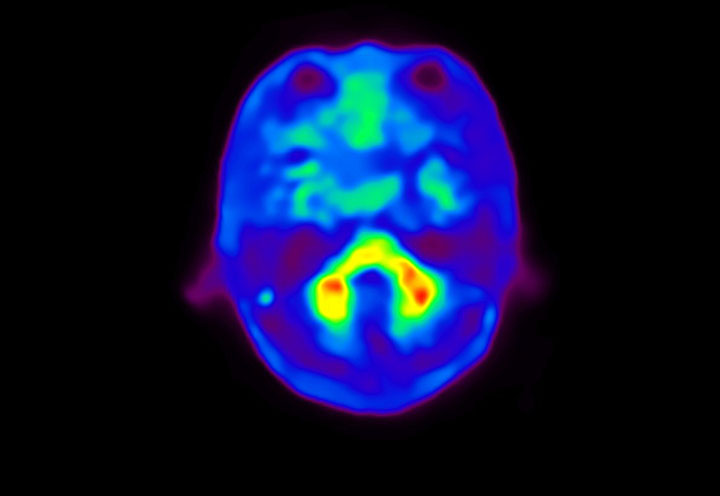

Head / Case4 : Amyloid

Courtesy : Kindai University Hospital

- Imaging protocol

- Injected dose: 3.21 MBq/kg, 18F-Flutemetamol

- Uptake time: 100 minutes

- Scan time: 20 minutes